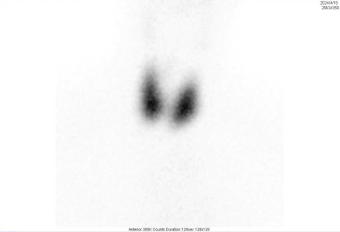

甲状腺显像异常图像(甲亢):